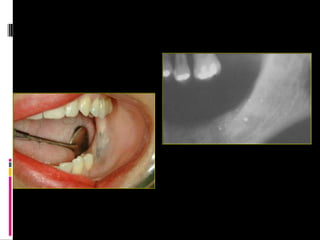

Acumulaciones de sustancias exógenas

 Tatuaje de amalgama: implantación de amalgama dental

en la mucosa oral originando una mácula de color negro,

azul o gris.También llamada: argirosis local.

Tatuaje de amalgama

Acumulaciones de sustanciasexógenas  Tatuaje de amalgama: implantación de amalgama dental en la mucosa oral originando una mácula de color negro, azul o gris.También llamada: argirosis local.